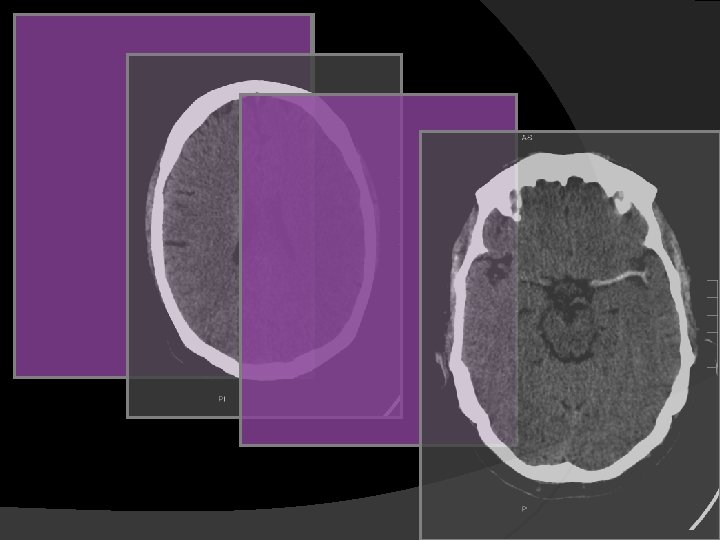

W 80, C 20 , SENSIBILIDAD 57% W 8, C 32 SENSIBILIDAD 71%. La detección precoz del infarto agudo en TC sin contraste puede mejorarse utilizando amplitudes de ventana variables para acentuar el contraste entre tejido normal y edematoso.

TC SIN CONTRASTE CUANTIFICACIÓN EXTENSIÓN DE LA ISQUEMIA “Regla del 1/3 del territorio de ACM”, ECASS (European Cooperative Acute Stroke Study), criterio de exclusión para fibrinolisis por el potencial riesgo de hemorragia. Estudios posteriores mostraron escasa correlación interobservador (variabilidad en el nivel de adquisición de las imágenes axiales). En 2001 fue propuesto el ASPECTS (Alberta Stroke Program Early CT Score) como medida cuantitativa en la valoración de la isquemia aguda en TC sin contraste.

ASPECTS Alberta Stroke Program Early CT Score M 1 M 2 M 3 M 4 M 5 M 6 CAUDADO LENTICULAR CÁPSULA INTERNA CÓRTEX INSULAR Se basa en un sistema de puntuación topográfico. El territorio de la ACM se divide en 10 regiones (10 puntos). Cada área afecta por la isquemia resta 1 punto. 0 puntos indican isquemia difusa del territorio de la ACM.

ASPECTS Por cada área afecta se resta un punto La puntuación se correlaciona Inversamente con el NIHSS Con el pronostico: muerte y dependencia Buena correlación interobservador Herramienta robusta, fácil y reproducible en la valoración del ictus. Pexman et al. AJNR 2001; 22: 1534– 1542.